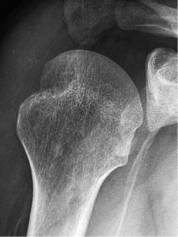

需要在肩关节内旋位、中立位、外旋位时分别拍摄3张正位X线,来评估有无Hill-Sachs损伤。

内旋位